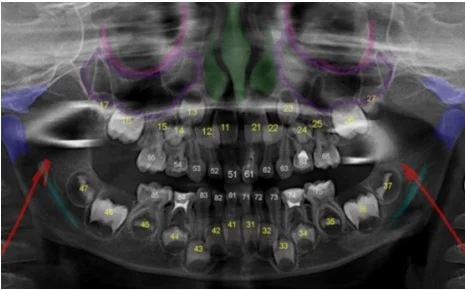

Ортопантомограмма в детской стоматологии

Ортопантомограмма - это один большой снимок на котором видны обе челюсти и, естественно, все зубы.

Помимо этого, на таком снимке можно увидеть:

- височно-нижнечелюстной сустав,

- гайморовы пазухи

- проекцию нижнечелюстного нерва.

В детской стоматологии обойтись без рентгена невозможно. Под корнями молочных зубов располагаются зачатки постоянных зубов, и прежде чем начинать их лечение, необходимо убедиться, что корни молочных зубов не начали рассасываться, и что проводимое лечение не повредит зачаткам постоянных зубов.

Панорамный снимок - это не то, на чем можно сэкономить. Малейшая ошибка в диагностике при отсутствии снимка - это риск серьезных упущений в лечении и дополнительных затрат.